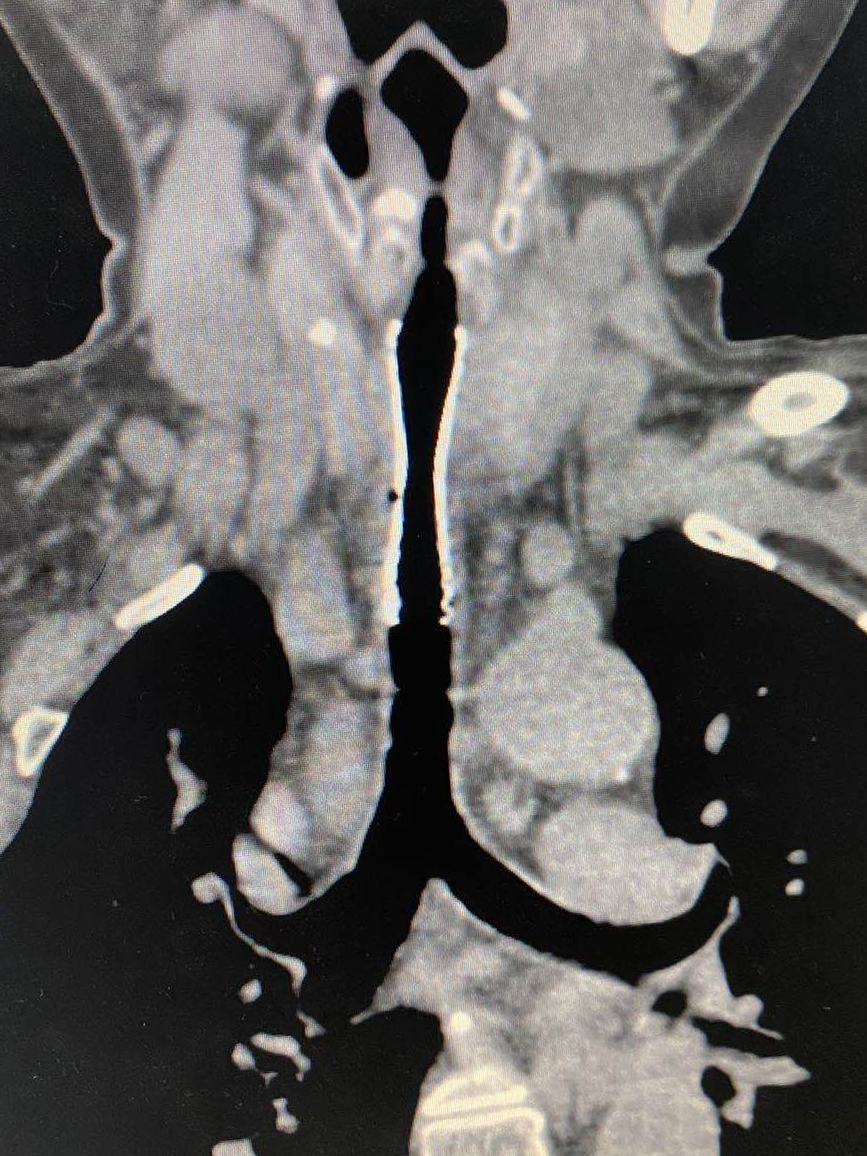

多方打聽下,他們慕名找到我院耳鼻咽喉頭頸外科專家汪文曉?;颊邭夤茏瞠M窄處僅6mm,而正常女性氣管直徑一般為12-15mm,隨時(shí)有窒息的可能??剖覉F(tuán)隊(duì)組織多學(xué)科會(huì)診,商討最優(yōu)治療方案??紤]到患者身體狀況不能接受全麻,最終慎重決定由放射科介入團(tuán)隊(duì)為其施行氣管支架植入術(shù)。

支架植入時(shí),患者的氣管會(huì)被臨時(shí)堵塞,如何冷靜、準(zhǔn)確地在短時(shí)間內(nèi)快速釋放支架,為患者撐起一線生機(jī),術(shù)者的技術(shù)和經(jīng)驗(yàn)至關(guān)重要。同時(shí),該患者氣管狹窄位置較高,若支架植入過低,則不能發(fā)揮效果;若支架植入過高,術(shù)后咽部刺激感明顯,依然不能提高生活質(zhì)量。因此,精確定位支架也是此次手術(shù)的一大難點(diǎn)。

但這些問題統(tǒng)統(tǒng)難不倒我們經(jīng)驗(yàn)豐富、身經(jīng)百戰(zhàn)的放射科介入團(tuán)隊(duì)。局麻下,他們通過導(dǎo)管將導(dǎo)絲順利插入氣管,再順沿導(dǎo)絲置入氣管支架套裝,準(zhǔn)確定位后快速釋放支架,全程僅用時(shí)3分鐘。支架完全打開,將只有一線生機(jī)的氣管牢牢撐開,吹風(fēng)樣的呼吸聲完全消失,患者瞬間恢復(fù)正常呼吸,效果立竿見影。